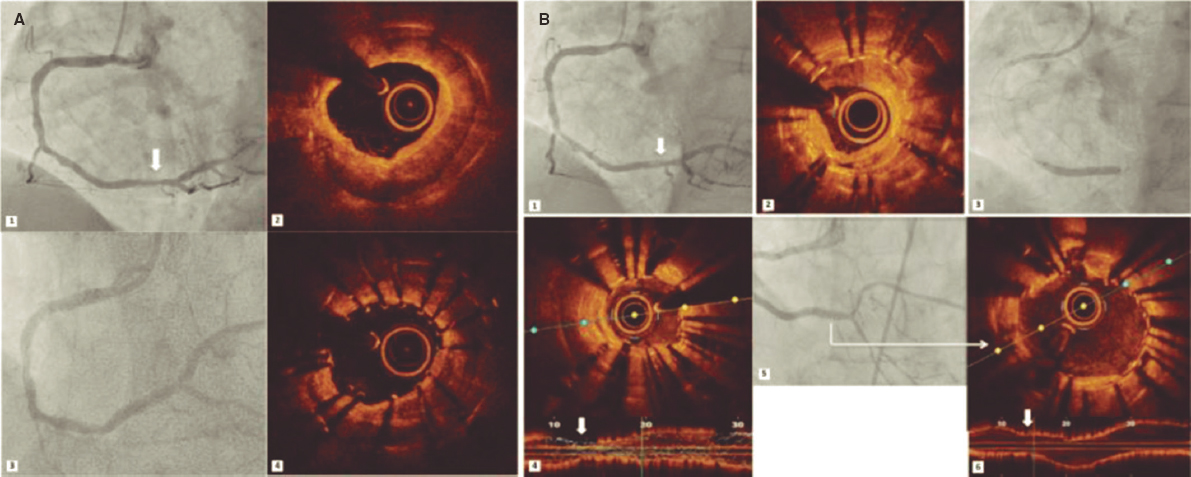

The 8-week follow-up revealed segmental alterations of contractility, lateral wall thinning, and fat transformation at posterior level in pig #1 and at posteroinferior level in pig #2 (figure 1). Ventricular volumes grew 10% and 7%, respectively.

Figure 1. Magnetic resonance imaging of animal #2. Short axis of the left ventricle. Presence of fat transformation at posterior level.